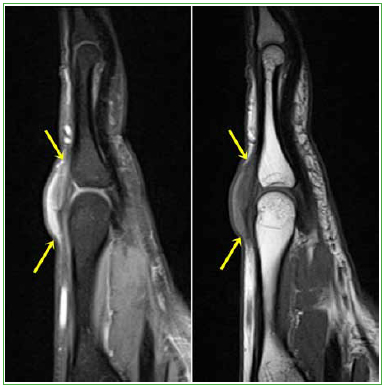

El examen de las otras regiones también mostró tumoraciones fusiformes en los tendones extensores del tercer dedo (Figuras 5 y 6) y el tríceps (Figuras 7 y 8), en forma bilateral.

Resonancia magnética, corte sagital potenciado en densidad protónica con supresión grasa (2100/25) y T1 (587/13) de la mano derecha. En el plano sagital, el nódulo (flechas amarillas) adquiere una morfología fusiforme.

Figura 7.

Resonancia magnética, corte axial potenciado en densidad protónica con supresión grasa (2770/39) del codo izquierdo. Se identifica una tumoración en el trayecto del tendón del tríceps, que se palpaba clínicamente.

Figura 8.

Resonancia magnética, corte sagital potenciado en densidad protónica con supresión grasa (3340/37) del codo izquierdo. Se distingue el patrón reticulado característico de este tipo de lesiones.